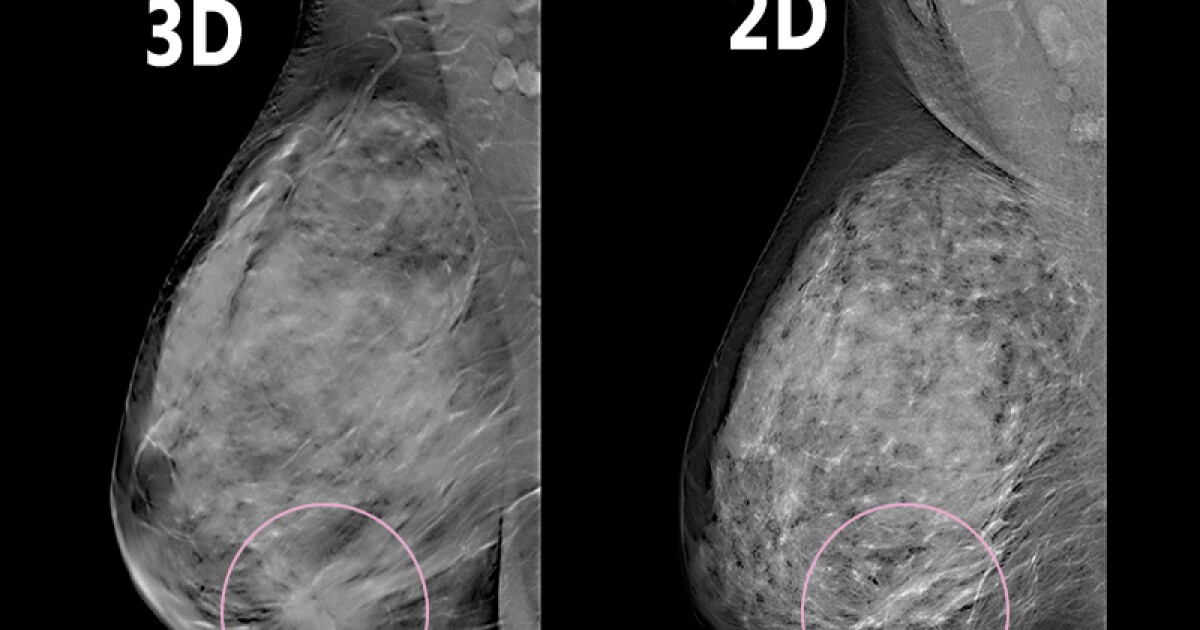

Uc Health Mobile Mammography . For every booking of 20 or more persons, the bus. All uc health breast imaging facilities, including the mobile diagnostic unit, use 3d mammography —an advanced screening tool which allows for. Our mammobus is the first mobile mammography unit in singapore that is equipped with full field digital mammography (ffdm) technology, which enables faster screening. Priority for resident of this grc) blk 285. The national healthcare group’s (nhg) mammobus, a mobile mammography service, is equipped with a digital. Our uc health mobile mammography van makes breast screening accessible to you near your work or home. Community mammogram screening event organised by tampines changkat wec (note: To encourage more women to go for a mammogram screening, singapore cancer society (scs), breast cancer foundation (bcf), and national healthcare group diagnostics (nhgd) are.

All uc health breast imaging facilities, including the mobile diagnostic unit, use 3d mammography —an advanced screening tool which allows for. To encourage more women to go for a mammogram screening, singapore cancer society (scs), breast cancer foundation (bcf), and national healthcare group diagnostics (nhgd) are. Our mammobus is the first mobile mammography unit in singapore that is equipped with full field digital mammography (ffdm) technology, which enables faster screening. The national healthcare group’s (nhg) mammobus, a mobile mammography service, is equipped with a digital. Our uc health mobile mammography van makes breast screening accessible to you near your work or home. Community mammogram screening event organised by tampines changkat wec (note: Priority for resident of this grc) blk 285. For every booking of 20 or more persons, the bus.